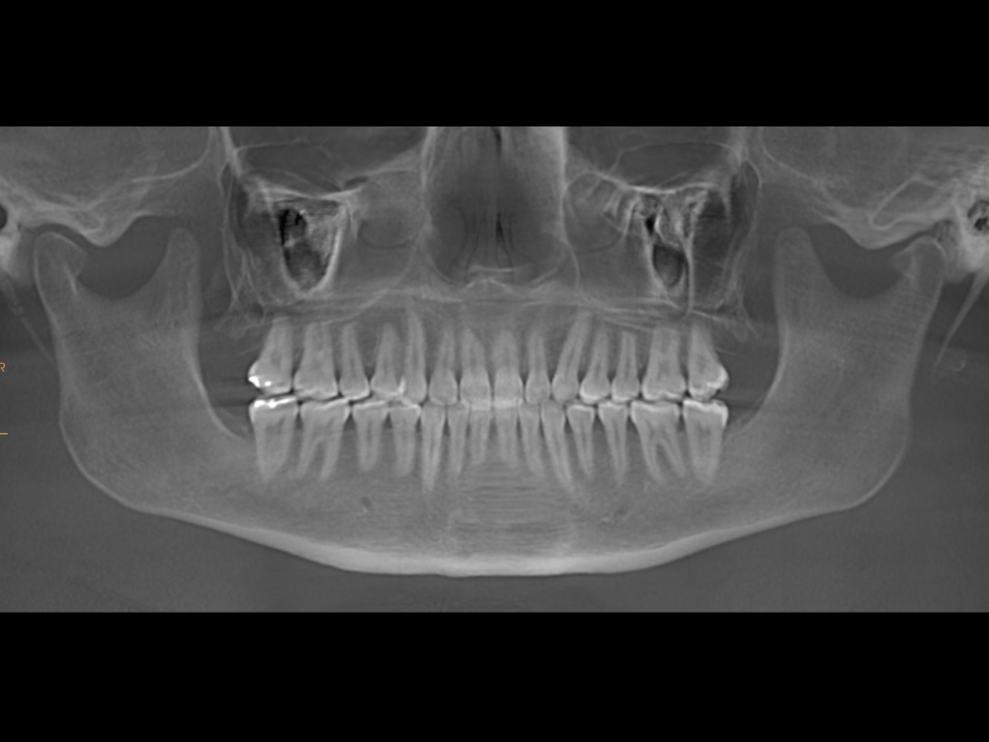

The final dental panoramic tomogram showed the correct levelling of the occlusal planes and root positions (Fig. 26). The final cephalometric tracing showed closure of the facial angle thanks to the posterior intrusion and mandibular auto-rotation (Figs. 27 & 28). Mandibular antero-rotation shortens the lower facial third, improving lip competence and ultimately the facial profile. The CBCT images of the TMJs showed the correct position of the condyles within the glenoid fossae (Fig. 29). When looking at the airway on the CBCT scan, we also saw an improvement of the patient’s airway (Fig. 30).